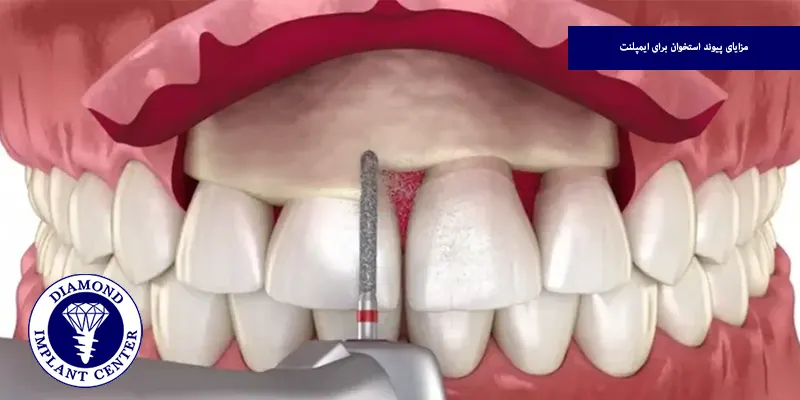

مزایای پیوند استخوان برای ایمپلنت

پیوند استخوان برای ایمپلنت دندانی یکی از مراحل کلیدی و تاثیرگذار در افزایش موفقیت و ماندگاری درمان ایمپلنت بهشمار میرود، در شرایطی که استخوان فک به هر دلیل تحلیل رفته یا ضعیف شده باشد، این روش بهعنوان پایهای محکم برای کاشت ایمپلنت عمل میکند و برخی از مهمترین مزایای این روش به شرح زیر است:

بازسازی فرم طبیعی صورت و فک

تحلیل استخوان فک نه تنها عملکرد دندانی را تحتتأثیر قرار میدهد، بلکه میتواند ظاهر چهره را نیز دچار تغییر کند و کاهش ارتفاع یا حجم استخوان ممکن است منجر به فرورفتگی گونهها، افتادگی لبها یا ناهماهنگی فکی شود و پیوند استخوان به بازسازی فرم طبیعی فک و حفظ زیبایی چهره کمک میکند و بهویژه در نواحی جلوی فک، نقش مهمی در نتایج زیبایی درمان دارد.